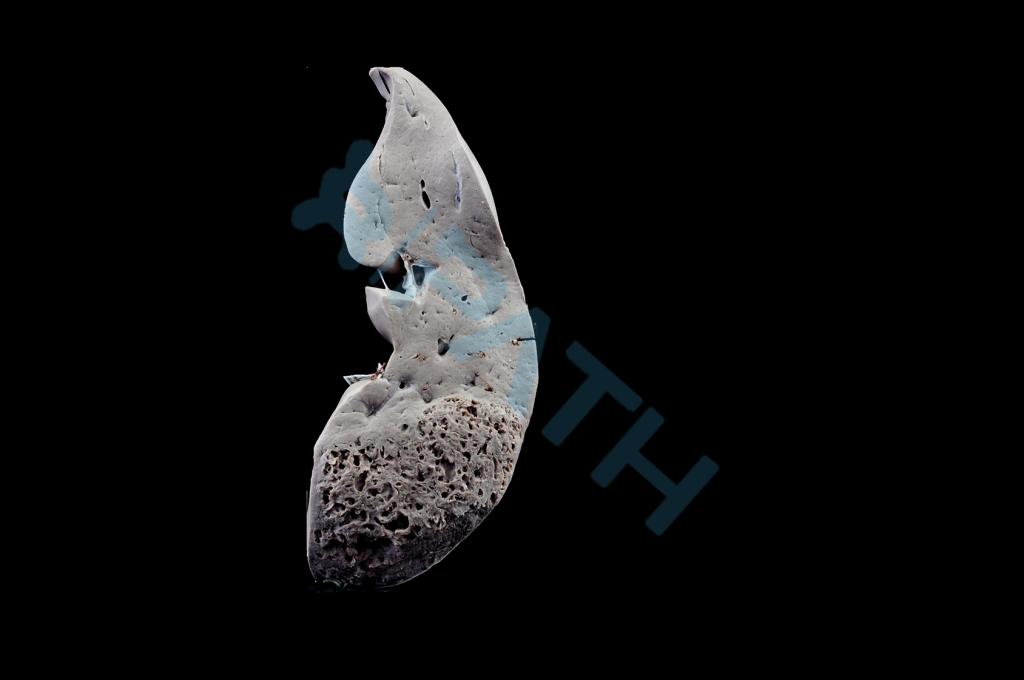

肺气肿

矽肺